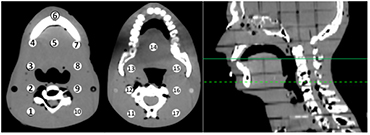

A treatment plan was created (Philips Pinnacle3, Fitchburg, WI) using a traditional lateral, parallel-opposed head and neck field technique; the dose was calculated on the 'patient' and recalculated on the 3D printed phantom; it is important to note that for the lateral parallel-opposed treatment plan the prescribed dose is 180 cGy per fraction which differs from the IMRT plan prescribed dose of 200 cGy described in section 2.3. Thermoluminescent detectors (TLD) were placed at equivalent positions in both phantoms; The TLD chips measure 3.2 × 3.2 × 0.9 mm and are composed of natural Lithium isotopic composition (TLD-100); three separate TLD measurements were collected and averaged for each of the 17 measurement locations. The locations of the TLD measurements are shown in figure 1. Similarity of the external geometry (defined at −500 HU) of 3D printed phantom and 'patient' was determined with the Jaccard Index (Jaccard 1912) and Dice Similarity Coefficient (DSC) (Dice 1945).

Figure 1. Locations of TLD measurement in the 'patient'. The axial slice where Regions 1–10 appear (left image) are indicated by the dashed line on the sagittal image (far right). The axial slice associated with Regions 11–17 are indicated by the solid line on the sagittal image.

The TLD measurements (see figure 1 and supplementary figure 2 (stacks.iop.org/PMB/59/5763/mmedia)) indicate that the use of ABS plastic and M3 mix resulted in acceptable soft-tissue equivalence; of the dose comparison points in figure 1, the greatest difference in calculated dose between the 'patient' and the 3D printed phantom was 1.8% (Region 11). For comparison, the deviation from the planned dose in the 3D printed phantom and the cylindrical diode array was 0.1% and − 23.1%, respectively. The dose difference of −23.1% is typical for the dose within the cylindrical diode array. In addition to Region 11, Region 4 and 17 also had differences in calculated dose greater than 1% of the prescribed dose. Regions 11 and 17 were located at the posterior field edge as indicated by the large standard deviation in calculated dose across the TLD measurement region. A point of note is that Regions 12–16 had a maximum percent difference of 0.6% with the presence of greater tissue density heterogeneities than Regions 11 and 17 (see figure 1). However, Region 4 is located at a bone-tissue interface and the greater difference in calculated doses could be due to the fact that the 3D printed phantom is made of a homogenous material. Therefore, modelling of different tissues may be beneficial, at least on a bulk density basis; at the very least, future investigation is needed. Considering a maximum difference of 1.8% between the calculated 'patient' and 3D printed phantom dose, the 3D printed phantom is sufficiently tissue equivalent for IMRT dose verification. If the 3D printed phantom is tissue equivalent to the degree that the resultant dose differences are limited to ±2% of the patient dose, then using a standard ±3% IMRT dose difference tolerance could assure a patient dose tolerance limit of ±5%; the mean absolute difference in calculated dose for Regions 1–17 was 0.7% ± 0.4%. It is important to note that air cavities in the sinuses were not sampled in Regions 1–17 and the authors acknowledge that those areas would likely have tissue equivalence differences greater than 2% if they were included in a treatment volume; the authors are actively working to include air cavities in the next version of 3D printed phantoms since air cavities can cause greater dose perturbations than bone in many cases.